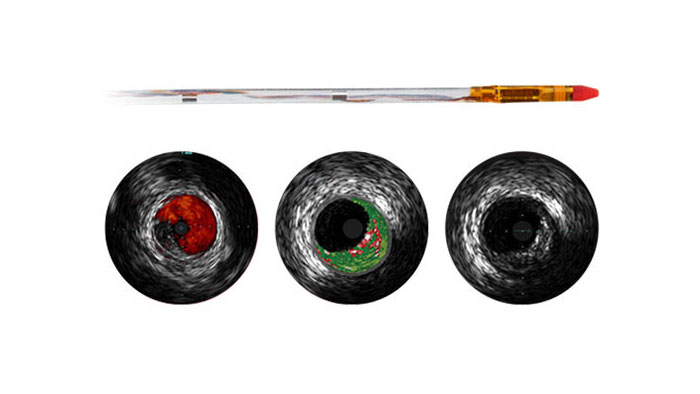

Представляем вашему вниманию проводник с датчиком давления десятого поколения Verrata Plus.

Цифровой катетер для ВСУЗИ Eagle Eye Platinum

Система для визуализации и ко-регистрации данных SyncVision

ВСУЗИ

Проводник с датчиком давления Verrata Plus

Надсекающий баллонный катетер AngioSculptX